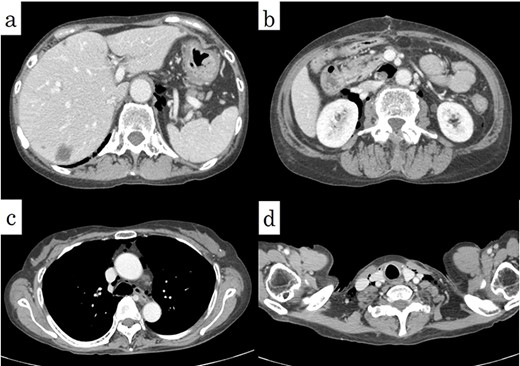

(a) The fixed sample showed a perforation site on the mesenteric side of the sigmoid colon (arrows). (b) The pathological specimen (haematoxylin and eosin, ×12.5) showed a rupture of the muscular layer, compatible with diverticular perforation.